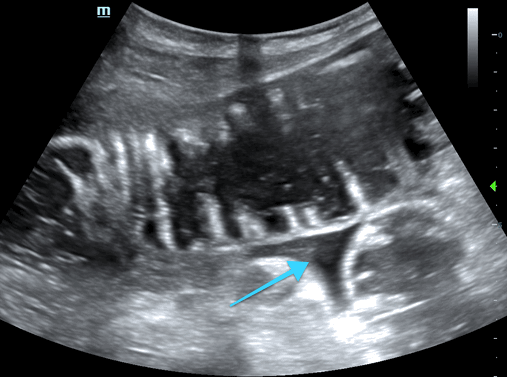

In the 3rd image, you see free fluid (arrow) between loops of bowel, which is associated with higher grade obstruction and poorer prognosis. This is referred to as the “tanga sign”  as the fluid often assumes a triangular shape similar to that of a bikini bottom (#funfact)

• Free fluid between loops of bowel - "tanga sign"

• *Free fluid is associated with higher grade obstruction and poorer prognosis